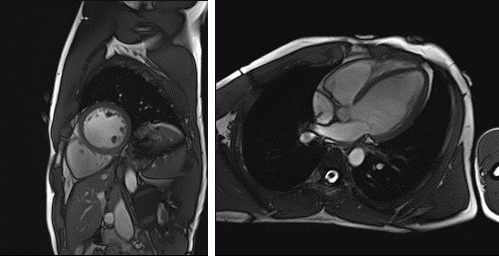

We have developed 3D heart detection and tracking approaches for both 3T and 7T scanners, which allow to void uncomfortable and unreliable prolonged breath hold for detailed cardiac MR acquisitions.

Renal imaging

Chronic kidney disease is a severe condition affecting one in ten people, which leads at end stage to a lifesaving need for dialysis and transplantation. Associated healthcare costs of this global burden are estimated to be more than 1 trillion USD worldwide.

The main challenge is that at early stages affected individuals are often unidentified in the clinics due to the limitations of blood and urine samples. Together with European and international partners (www.renalmri.org) we are optimising non-invasive MRI techniques to improve diagnosis of chronic kidney disease.